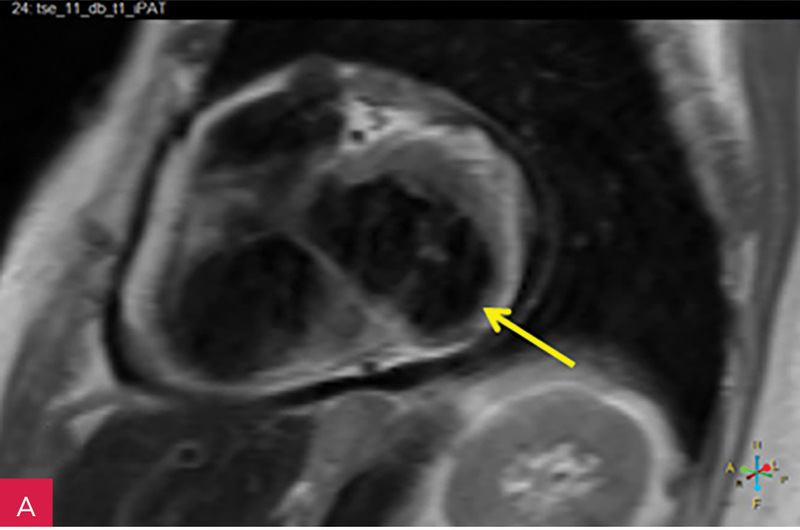

Rycina 7A-D. Obrazy rezonansu magnetycznego w osi krótkiej na wysokości pierścienia mitralnego: czarnej krwi T1-zależne TSE (A); czarnej krwi T2-zależne HASTE (B); T1-zależne echa gradientowego dynamicznie podczas podawania środka kontrastowego (C); sekwencja SSFP, pojedynczy obraz w osi krótkiej (D). W dolno-bocznej części pierścienia mitralnego od strony światła lewej komory zmiana (strzałki) niskosygnałowa we wszystkich ważeniach sygnału

Rycina 8A, B. Obrazy rezonansu magnetycznego w projekcji pięciojamowej (A) i dwujamowej (B) z późnym wzmocnieniem kontrastowym – widoczna zmiana ulegająca brzeżnemu wzmocnieniu kontrastowemu. Całość obrazu wskazuje na serowate zwapnienie pierścienia mitralnego (CCMA)

W celu weryfikacji zmiany i oceny charakterystyki tkanki wykonano CMR,

w którym stwierdzono w dolno-bocznej części pierścienia mitralnego od strony światła lewej komory zmianę odpowiadającą morfologicznie CCMA, obejmującą 7,3 cm obwodu pierścienia mitralnego, o grubości w osi krótkiej do 25 mm, w osi długiej do 21 mm; zmiana ulegała brzeżnemu wzmocnieniu kontrastowemu i powodowała ograniczenie ruchomości tylnego płatka zastawki mitralnej, obejmowała struny ścięgniste mięśnia brodawkowatego tylno-przyśrodkowego. Ponadto uwidoczniono znacznie powiększone przedsionki z istotnym włóknieniem – jak w restrykcji (ryc. 7, 8).